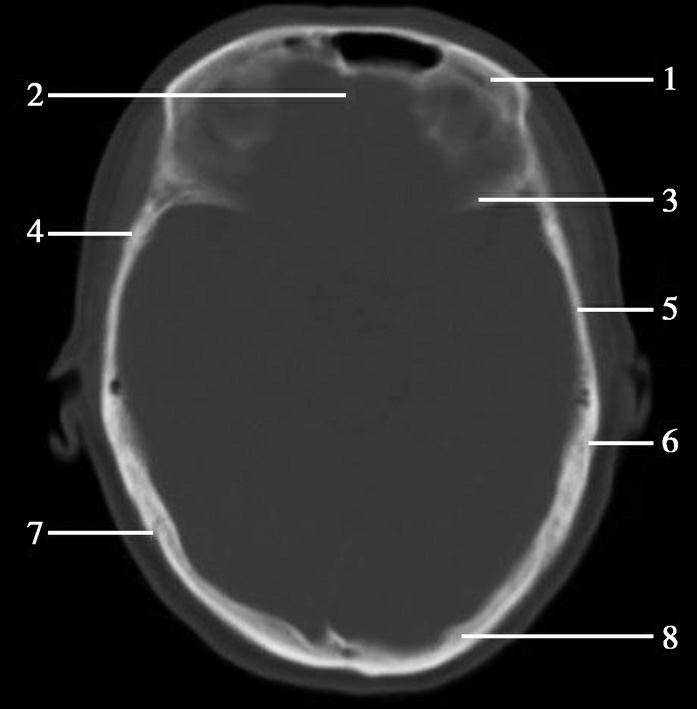

第三脑室正常成人前后径约12mm,左右宽约5mm,上下径也约为12mm。侧脑室后角两侧有时大小不等,右侧后角上下径约为38mm,左右径约为20mm;左侧后角上下径约为28mm,左右径约为15mm。测量双侧侧脑室前角间径与同平面脑横径的比值(R),正常平均值为30%。轻度扩大时为31%~39%,中度扩大为40%~46%,重度扩大时>47%。脑积水或脑萎缩等病理情况下脑室系统会扩大。不同年龄组正常脑室系统测量值存在差异,整体表现出测量值随着年龄增大而增大的趋势(图1-2-83、图1-2-84)。

图1-2-83 第三脑室测量

a线.第三脑室前后径;b线.第三脑室宽径

图1-2-84 侧脑室测量

R=双侧侧脑室前角间径(a)/同平面脑横径(b)